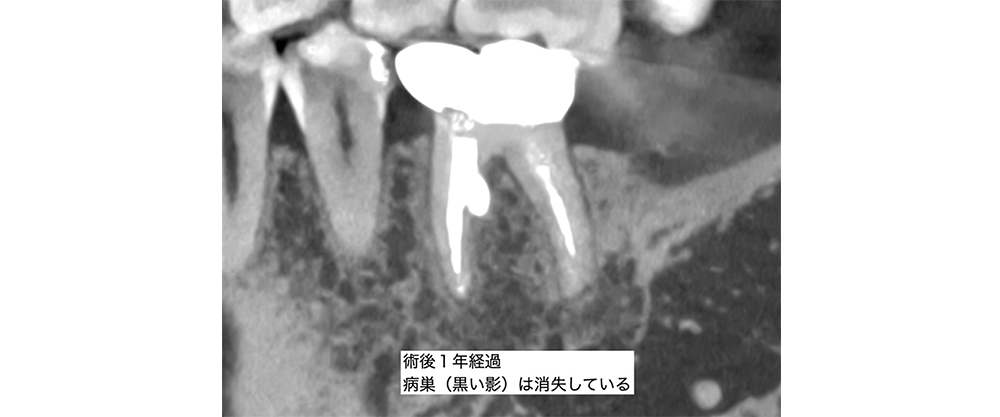

金山デンタルクリニックでは、治療の前に必ずCT撮影を行い、神経の本数や根の形、病変の大きさを正確に診査。治療の可能性や成功率まで含め、CTの画像を見せながら丁寧にご説明しています。治療後の経過もマイクロスコープやCT画像をお見せしながら、ご説明させていただきます。